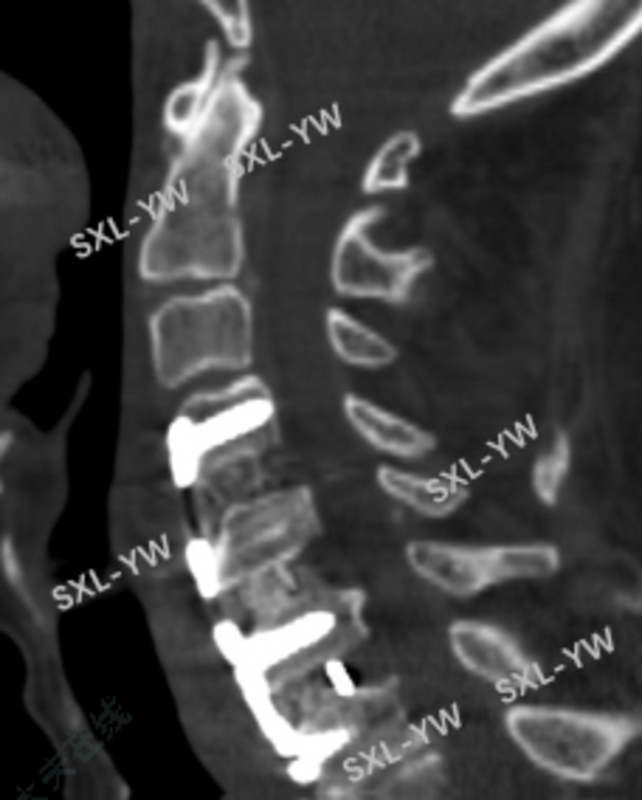

术前CT提示:严重颈椎退变,椎体前后缘大量骨赘增生,椎间隙高度完全塌陷并骨性融合。

术后CT:椎体后缘骨赘切除彻底,减压区很大,呈锥形。